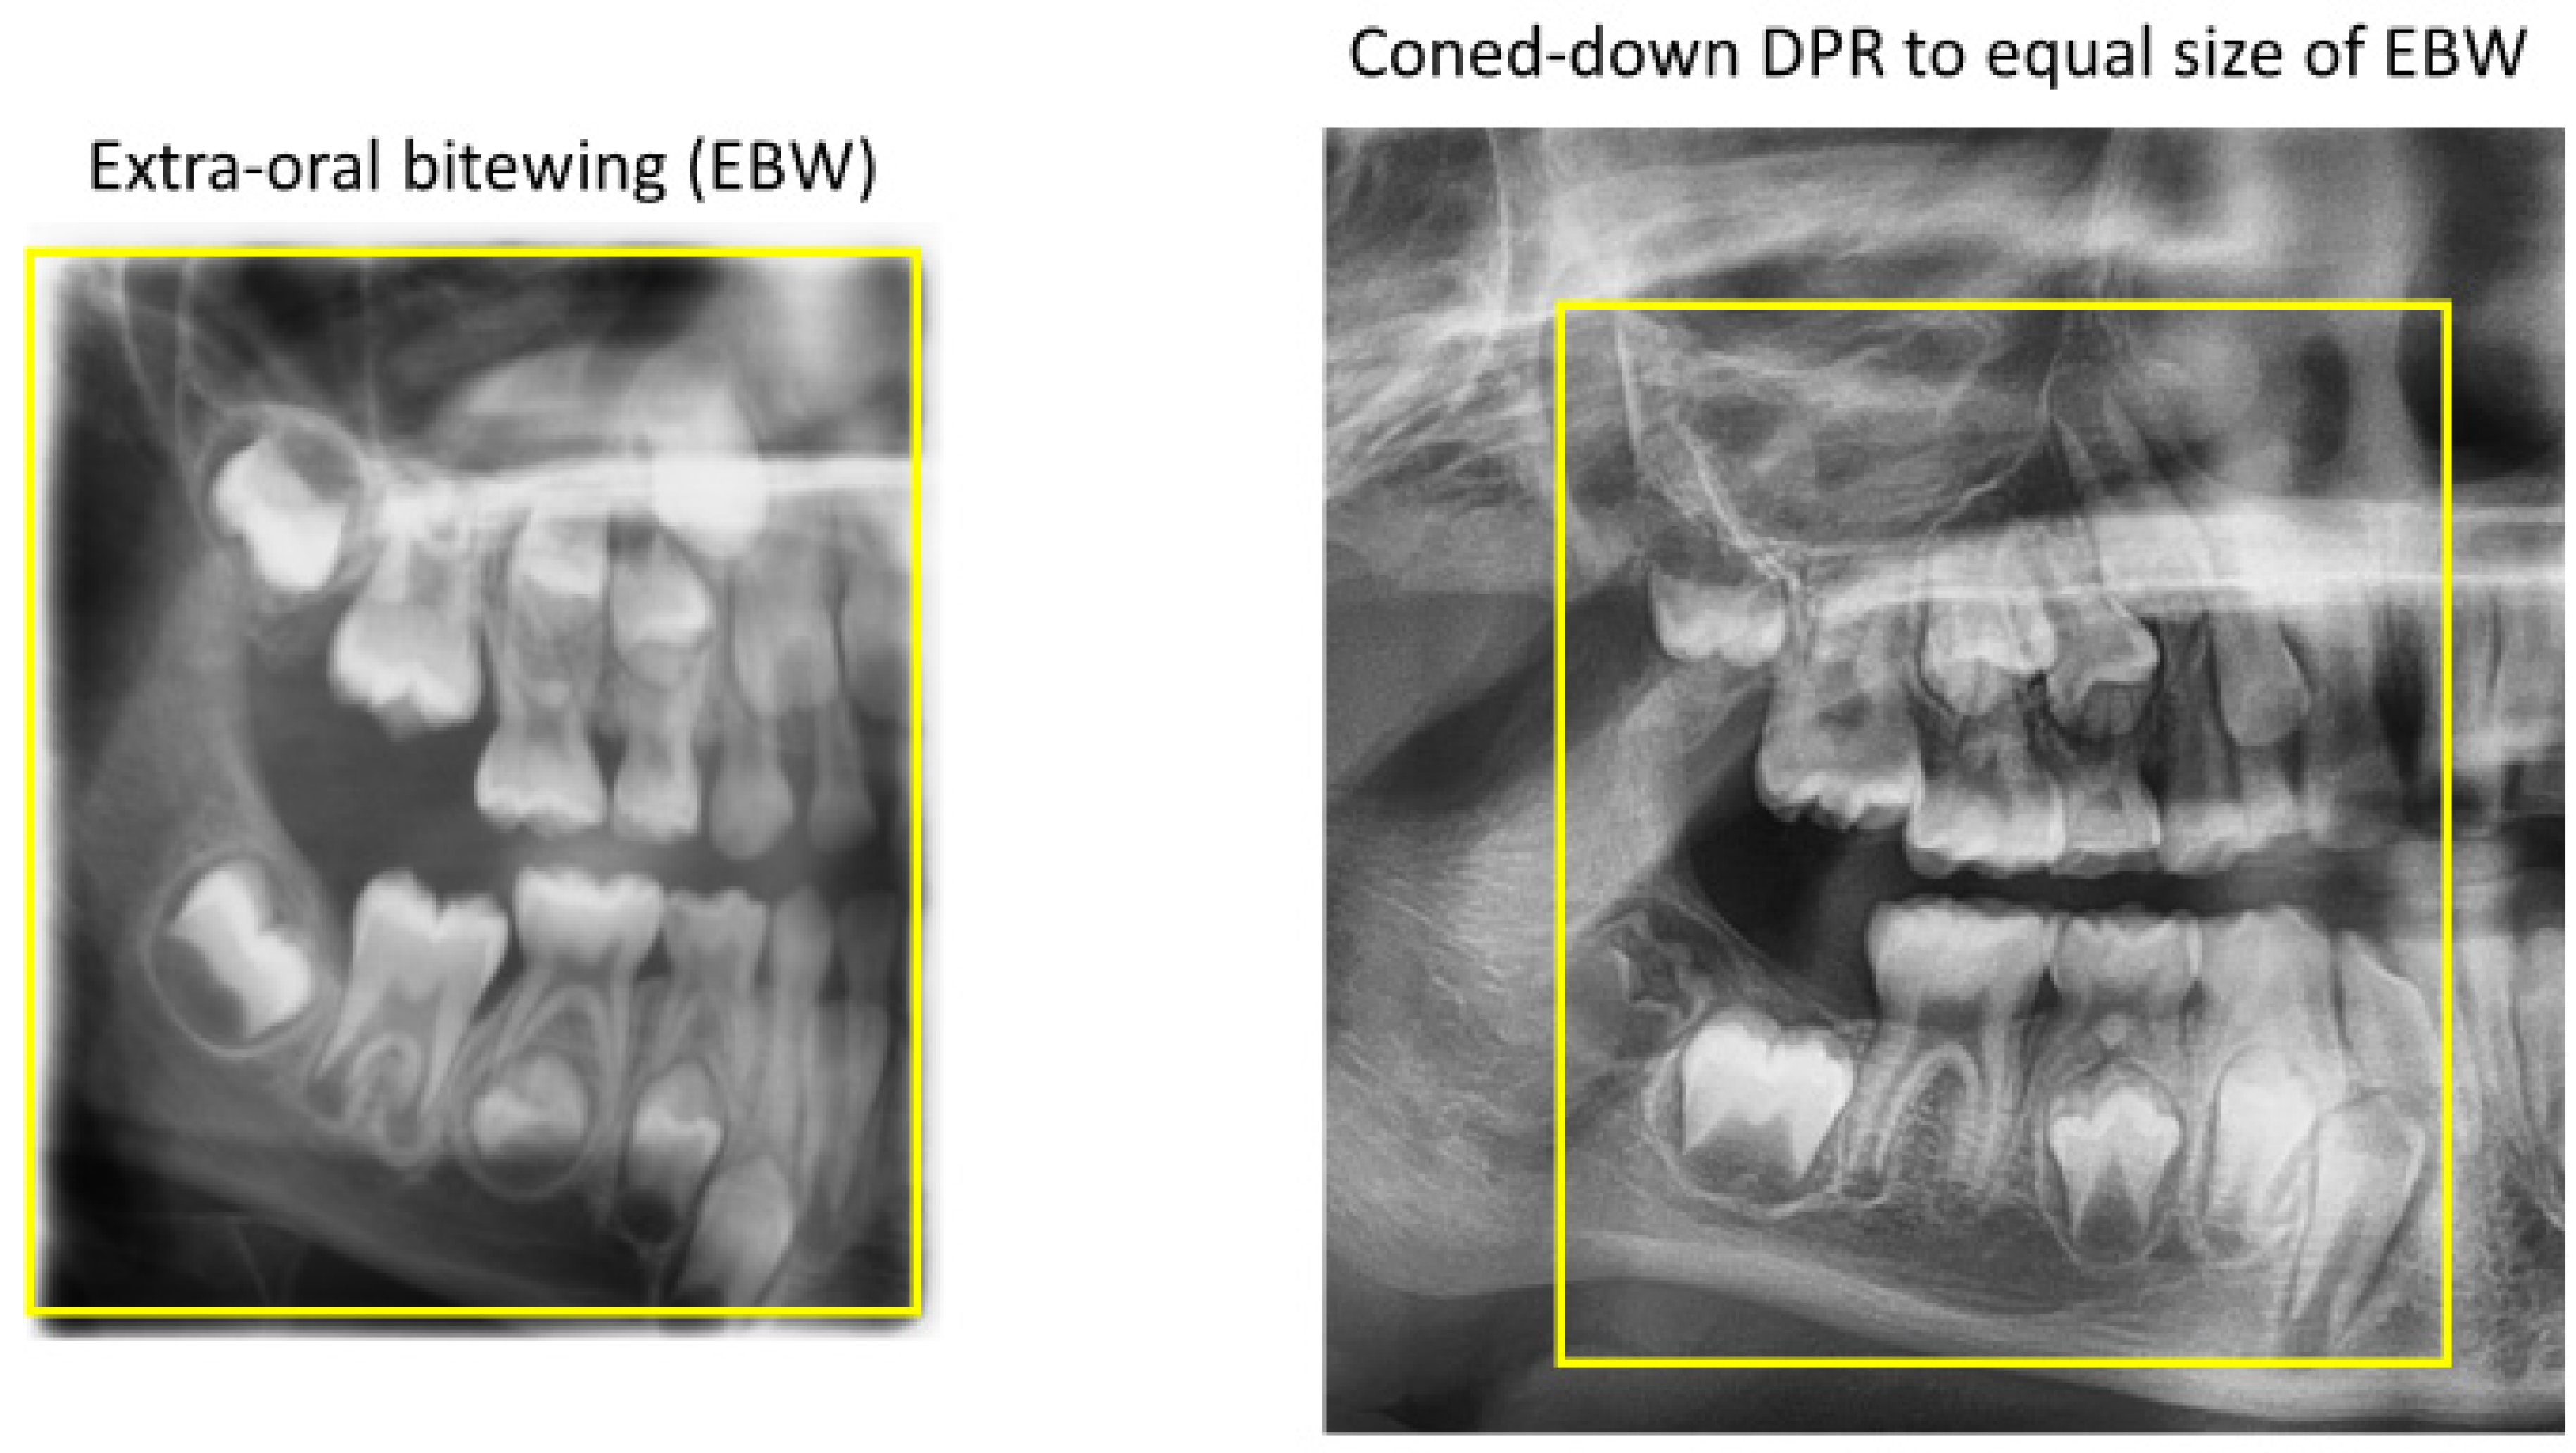

Extra-Oral Bitewing

- Chan, M.; Dadul, T.; Langlais, R.; Russell, D.; Ahmad, M. Accuracy of extraoral bite-wing radiography in detecting proximal caries and crestal bone loss. J. Am. Dent. Assoc. 2018, 149, 51–58. [Google Scholar] [CrossRef] [PubMed]